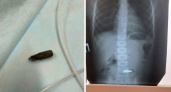

Врачи извлекли биту от шуруповерта из желудка 4-летнего ребенка